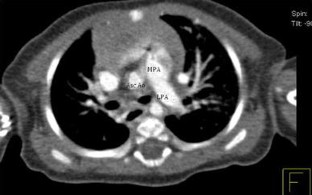

Absence of the Right Pulmonary Artery Associated With a Partial Anomalous Pulmonary Venous Connection

Unilateral absence of a pulmonary artery is a rare anomaly. Patients may present with hemoptysis, recurrent respiratory infections, pulmonary hypertension, or congestive heart failure. This report describes the case of a missing right pulmonary artery associated with anomalous left pulmonary venous connection not previously described in the medical literature.

Fig. 2